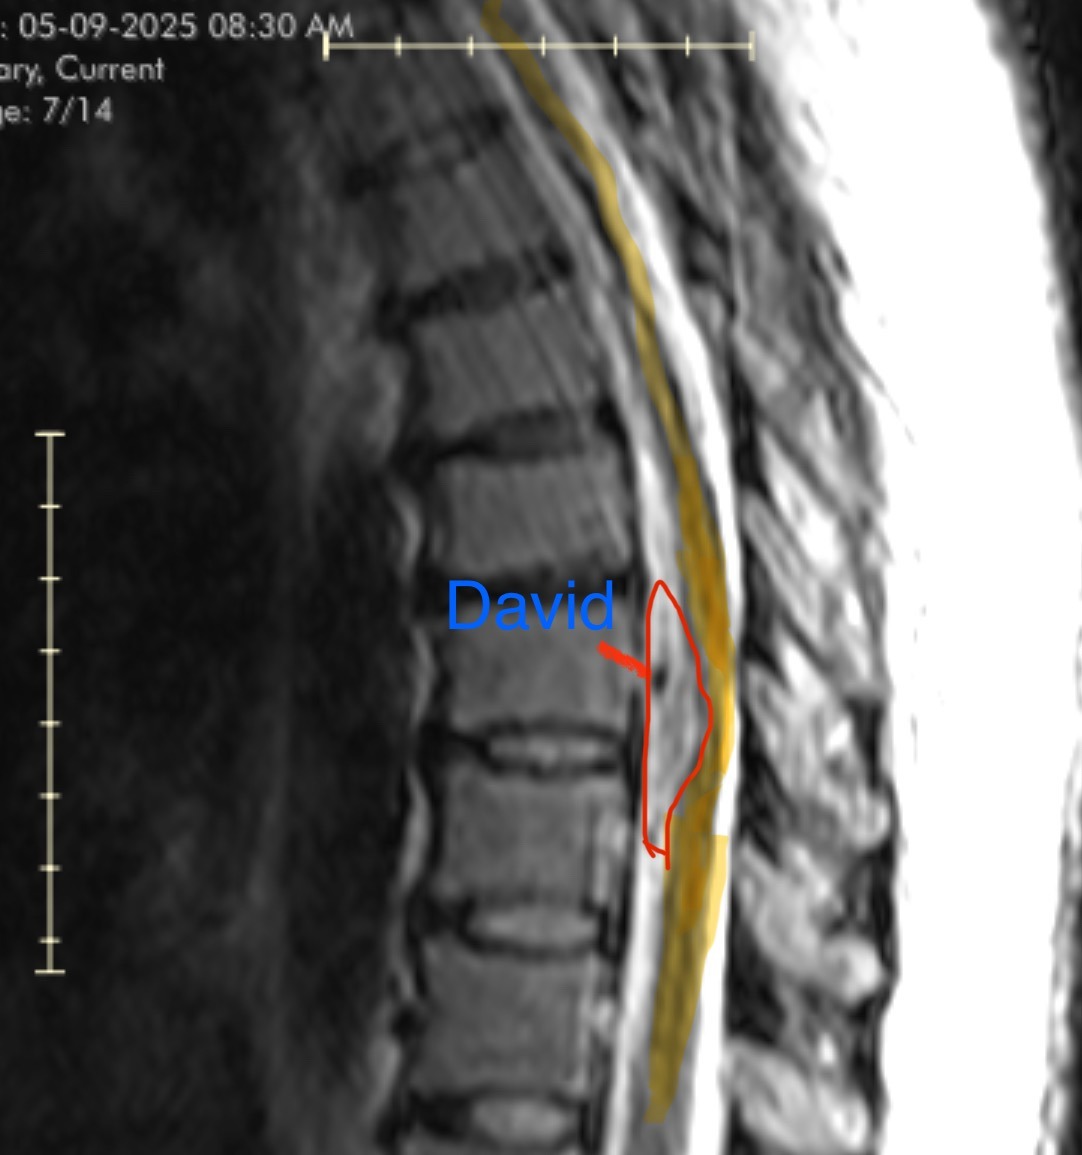

Meet David, Sam’s Malignant Melanotic Nerve Sheath Tumor

Malignant melanotic nerve sheath tumor (MMNST) is an extremely rare form of cancer that develops in the cells surrounding nerves. Because it is so uncommon, treatment can be complicated, expensive, and often requires specialized care. Since MMNST is a mouthful, we have dubbed Sam’s tumor as David.